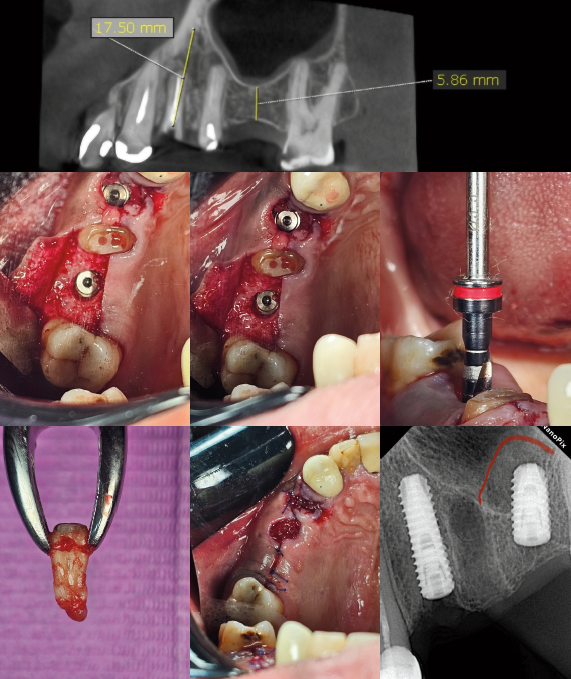

زراعة الأسنان المتقدمة

تقنيات زراعة الأسنان بأحدث الطرق والمواد المتطورة لضمان النجاح والاستقرار طويل المدى

إعادة تكوين الأنسجة الموجهة

تقنية متقدمة لإعادة بناء العظام والأنسجة الداعمة للأسنان باستخدام أغشية ومواد بيولوجية متطورة